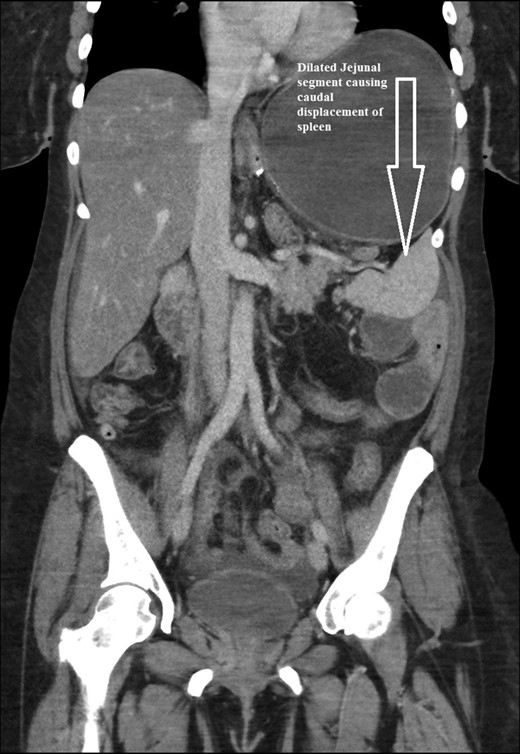

CT scan of her abdomen and pelvis revealed findings of previous gastric bypass with gastric pouch severely dilated and air-fluid levels measuring up to 17 cm. The excluded portion of the stomach was noted to be decompressed as a result of dilated gastric pouch. The proximal to mid small bowel was fluid-filled and severely dilated to approximately 4 cm. Distal small bowel and colon were decompressed. There was no evidence of pneumoperitoneum. Based on these findings initial diagnosis was presumed to be gastric outlet obstruction with dilated gastric pouch. Fluid hydration and nasogastric tube decompression was continued. Patient was prepared to be taken to the operation room for emergent diagnostic laparoscopy.

The intraoperative findings were not consistent with the radiological findings (Figs 1–4). As shown in the CT scan of abdomen and pelvis; multiple loops of dilated small bowel were seen, more predominantly dilated and matted bowel complex just above the spleen. The dilated bowel complex was decompressed using needle aspiration to help reduction of the bowel loops. The ileo cecal junction was then identified and traced back to the perisplenic hilar region. The trifurcation of three bowel loops (Roux limb, biliopancreatic limb and common limb) were identified with identification of ligament of Treitz. The prior gastric bypass was of ante colic- ante gastric type and Peterson’s defect was not closed. The above described bowel trifurcation had sunken postero- inferior to the spleen and had herniated through a potential space underneath the spleen and torsed around the splenic vessels and hilum. This picture was consistent with perisplenic small bowel volvulus. As noted earlier there was a massively dilated proximal small bowel segment above the spleen, displacing it caudally. Careful adhesiolysis was performed inferior to the spleen to release the segment of the trifurcation. The bowel segments once reduced were assessed and appeared viable. Of note, the spleen appeared better perfused after reduction. The remnant hernia defect of size 2 × 3 × 2.5 cm around the hilar region was then approximated using interrupted non-absorbable sutures. Enterotomy at the decompression site was closed with non absorbable suture. All potential sites of IH were re-examined and there was no evidence of any other internal herniation. Coelomic cavity was thoroughly irrigated and operation concluded successfully. Postoperative hospital stay was uneventful, and the patient was discharged home after two days.

Coronal CT scan of abdomen and pelvis showing Dilated jejunal segment causing caudad splenic displacement.